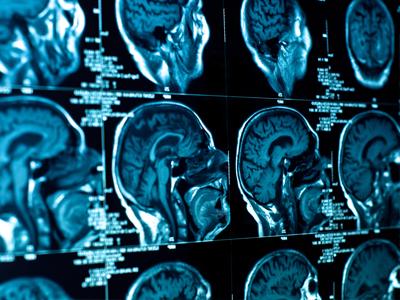

A Napoli il XV Congresso mondiale di Neuroradiologia interventistica

Si svolgerà a Napoli dal 21 al 24 ottobre il XV congresso della Società Mondiale di Neuroradiologia Interventistica (Wfitn - World Federation Inte...